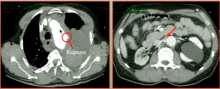

Davide Pacini of the S. Orsola-Malpighi Hospital, Bologna, Italy, poses the question: should the aortic arch be replaced during acute type A dissection repair? Dr. Pacini discusses the role of the frozen elephant trunk in these cases.